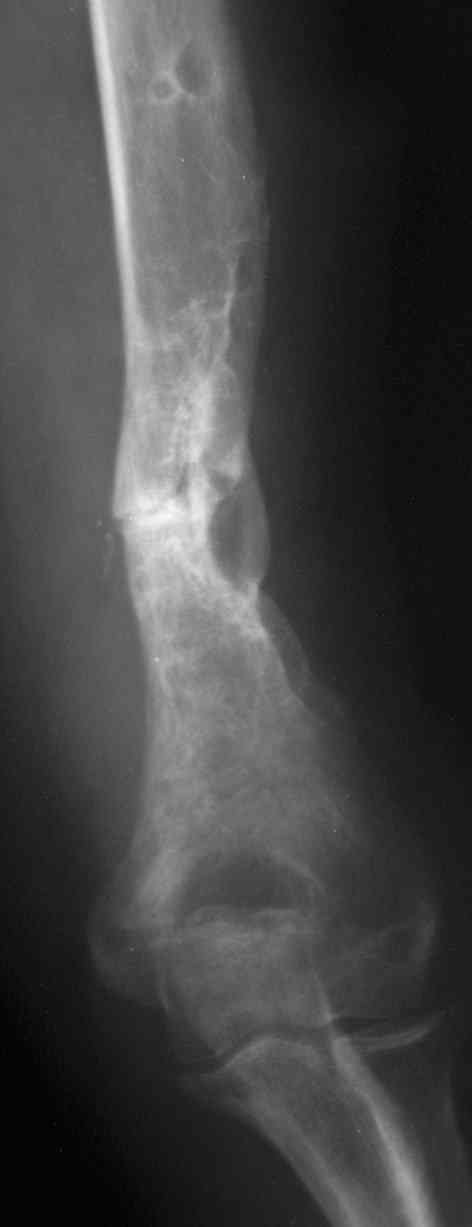

Рентгеновская версия реконструкции. хронология:

после операции, 2 мес. после операции, через 1 год

Движения в полном объеме восстановлены к 2 мес. после операции. Если надо могу показать мультик. Сейчас уже прошло более 3 лет, больная не

показывается. Успехов ЛАФ.